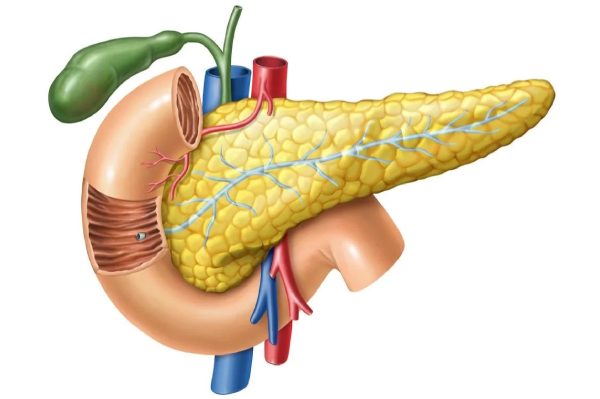

Pancreas

Minimally invasive pancreatectomy

A minimally invasive pancreatectomy is a surgical procedure that involves the removal of part or all of the pancreas through small incisions made in the abdomen. This procedure is performed to treat a number of conditions that affect the pancreas like tumours, inflammation, severe trauma, etc. when other treatment methods are unsuccessful. Minimal blood loss, shorter hospital stay, quicker recovery are some of the benefits of minimally invasive pancreatectomy.

Whipple procedure (minimally invasive pancreatoduodenectomy)

A Whipple procedure often called pancreatoduodenectomy, is a surgical operation to remove the head of the pancreas, the upper section of the small intestine (duodenum), the gallbladder and the bile duct. When this surgery is performed through a laparoscope or robotic-system, it is called minimally invasive pancreatoduodenectomy. Most often, this procedure is used to treat Pancreatic cancer, Pancreatic cysts, Pancreatitis, Pancreatic tumors, Bile duct cancer, Trauma to the pancreas or small intestine and small bowel cancer.